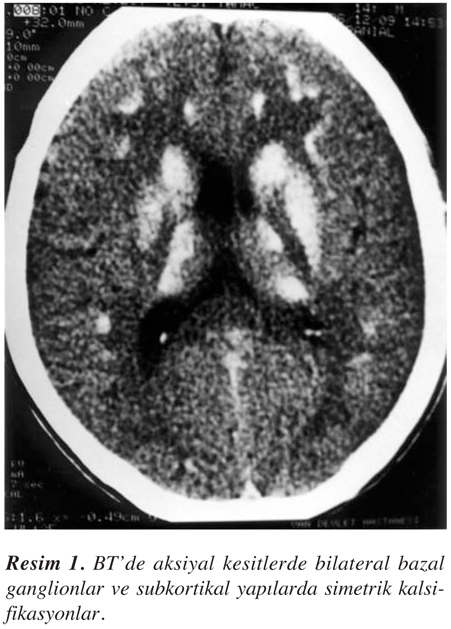

Nörolojik muayenede bilinç açık ve koopere idi. Yapılan kısa mental durum testinde (mini mental state- MMST), mental işlevlerde orta derecede bozukluk saptandı. MMST skoru 23 bulundu. Bu tabloda dikkat ve konsantrasyon bozukluğu gibi daha çok frontal işlev bozukluğu hakimdi. Derin tendon refleksleri hipoaktifti. Her iki gözde katarakt mevcuttu. Serebellar testlerde bilateral hafif dismetri ve disdiadokokinezi saptandı. Tonus üst ekstremitelerde hafif artmıştı. Duyu ve motor muayene normaldi. Patolojik refleks saptanmadı. EEG’de hafif ve yaygın organizasyon bozukluğu zemininde bilateral temporal ve frontal bölgelerde intermittan ritmik delta yavaşlamaları gözlendi. BT incelemesinde bazal ganglionlarda belirgin olmak üzere her iki serebral hemisferde subkortikal bölgelerde ve serebellar hemisferlerde yaygın, yoğun ve simetrik kalsifikasyonlar saptandı (Resim 1 ve Resim 2).

İntrakranial kalsifikasyonlar, hipoparatiroidinin oldukça sık görülen bir özelliğidir ve başlıca bazal ganglionlarda görülür (1,3,6-8). Ayrıca serebellar hemisferlerde, dentat nukleusta, nukleus ruberde, hipokampusta ve serebral kortekste de ortaya çıkabilir (1,2,4-7). Topografik olarak başlıca lokalize, multipl yama tarzında ve bilateral simetrik kalsifikasyonlar olarak sınıflandırılırlar. Bazal ganglion kalsifikasyonları en sık globus pallidusta görülür. Yaşlılarda fizyolojik olarak punktat ve hafif düzeyde bulunabilir. Putamen lokalizasyonlu olanlarda hipoparatiroidi veya psödohipoparatiroidi düşünülmelidir (1).

Semptomların genellikle lokalizasyonla ilişkili olmadığından sözedilmekle birlikte parkinsonizm, koreatetoz ve tremor gibi ekstrapiramidal bulgulara sık rastlanır (6,7,11,12). BT’deki kalsifikasyon lokalizasyonları her zaman klinik bulgularla korelasyon göstermese de (12), manyetik rezonans ile yapılan bir çalışmada, nörolojik manifestasyonların kalsifikasyonların lokalizasyonu ile sıkı ilişkisi vurgulanmaktadır (11). Hipoparatirodizmde serebellar hemisferler ve subkortikal bölgelerde de kalsifikasyon bulunabilir. Bizim olgumuzda da bilateral ve simetrik olmak üzere bu bölgelerde kalsifikasyon vardı. Oysa Fahr hastalığında daha çok bazal ganglion tutulumu belirgindir ve subkortikal beyaz cevher korunmuştur. Ayrıca Fahr hastalığında otozomal dominant veya resessif geçiş sözkonusu olup paratiroid metabolizması bozukluğu olmadan kalsiyum ve demir depositleri birikmektedir (1,8,11,13). Olgumuzun aile öyküsünde böyle bir hastalığa rastlanmamıştır. Kafa içi basınç artışı ve papil ödemi, hipoparatiroidili bazı olgularda rastlanabilir. Psödotümör serebri, serum kalsiyumunun düzeltilmesi ile normale döner (3,8).